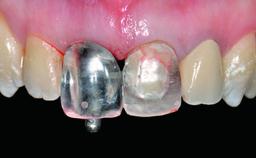

Abutment Type CAD/CAM

Prosthesis Type FDP

Loading Protocol Conventional or early

Retention Screw-retained Screw-retained

Provisional Implant-Supported Prosthesis Prosthodontic margin > 3 mm apical to mucosal margin Prosthodontic margin > 3 mm apical to mucosal margin